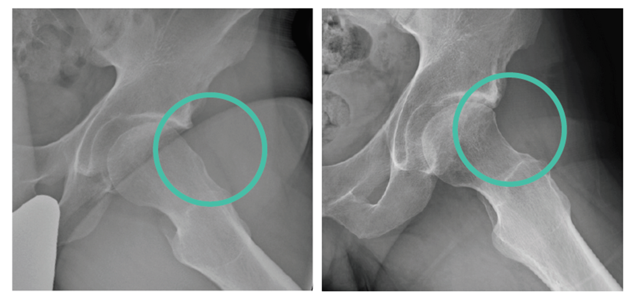

L'Impingement femoro-acetabolare è una condizione patologica che interessa l'articolazione coxo-femorale ed è caratterizzata dal contatto anomalo tra la testa femorale e il bordo acetabolare (fig. 2), con il conseguente aumento della frequenza di lesioni cartilaginee e di alterazioni del labrum acetabolare, struttura fibrocartilaginea paragonabile al menisco che funge da guarnizione per la testa del femore aumentando la congruenza articolare.

Si distinguono due tipi di conflitto femoro-acetabolare, il PINCER e il CAM (figg. 2 e 3), che possono manifestarsi isolatamente o in associazione.

Il PINCER impingement è sostenuto da un eccesso di copertura acetabolare, mentre il CAM impingement origina da un'anomalia morfologica della giunzione testa-collo, con riduzione della sfericità e presenza di una protuberanza generante attrito detta "bump".

In entrambi i casi, la non perfetta conformazione dei capi articolari riduce l'escursione che il femore può eseguire prima di "urtare" i bordi dell'acetabolo generando il "conflitto".